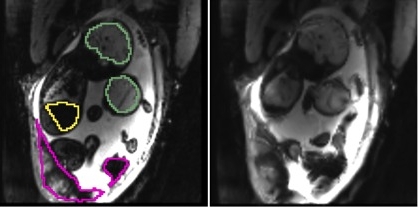

Case 1 Case 2

, manual , manual

, manual , automatic , manual , automatic

(a) Placentae

(b) Fetal brains

(c) Fetal livers

Fig. 2 illustrates results for two example cases from the study. We observe that the reference frame was warped accurately by the algorithm to represent a frame in the series that is substantially different in the regions of the placenta and the fetal liver. The delineations achieved by transferring manual segmentations from the reference frame to the coordinate system of the current frame ( in the figure) are in good alignment with the manual segmentations for the current frame. Fig. 3 reports volume overlap statistics for the placentae, fetal brains, and fetal livers, for each case in the study. We observe that temporal alignment improves volume overlap in important ROIs and offers consistent improvement for all cases over pairwise registration to the reference frame. We also note that temporal alignment offers particularly substantial gains in cases with a lot of motion, i.e., low original volume overlap.